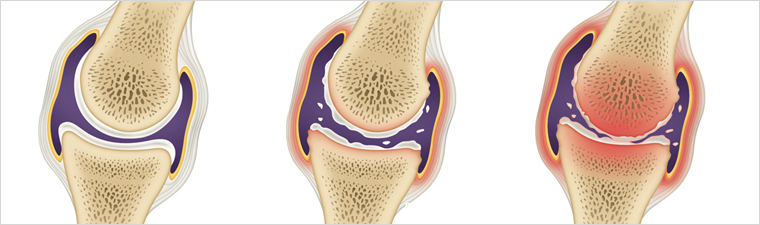

돼지고기, 소고기, 양고기 등 붉은 고기는 풍미가 좋아 자주 찾게 되지만 퓨린 함량이 높아 통풍 환자에게 문제를 일으킬 수 있습니다. 퓨린이 분해되면 요산이 생성되므로 붉은 고기를 지나치게 섭취하면 혈중 요산 수치가 오르고 통풍 발작을 유발할 가능성이 커집니다. 완전히 끊기 어렵다면 섭취 빈도와 양을 줄이는 것이 바람직합니다.

튀긴 음식은 트랜스지방과 포화지방이 많아 요산 배출을 방해하고 전신 염증을 악화시킬 수 있습니다. 치킨, 감자튀김 등 흔히 즐기는 튀김류는 통풍 증상을 악화시킬 위험이 큽니다. 통풍 환자라면 튀긴 음식 섭취를 자제하시는 편이 안전합니다.

10. 술

블루베리, 체리, 라즈베리 등 베리류는 항산화 성분이 풍부하여 염증을 완화하고 요산 배출을 돕는 효과가 알려져 있습니다. 꾸준히 섭취하면 통풍 통증 완화에 도움이 될 수 있습니다.

수박은 수분 함량이 매우 높아 자연스러운 이뇨 작용을 도와 요산이 소변으로 배설되기 쉬운 환경을 만듭니다. 또한 항염 효과가 있어 급성 통풍의 염증과 부종을 완화하는 데 도움이 될 수 있습니다. 다만 과도한 당분 섭취를 피하기 위해 적당량을 유지하는 것이 좋습니다.